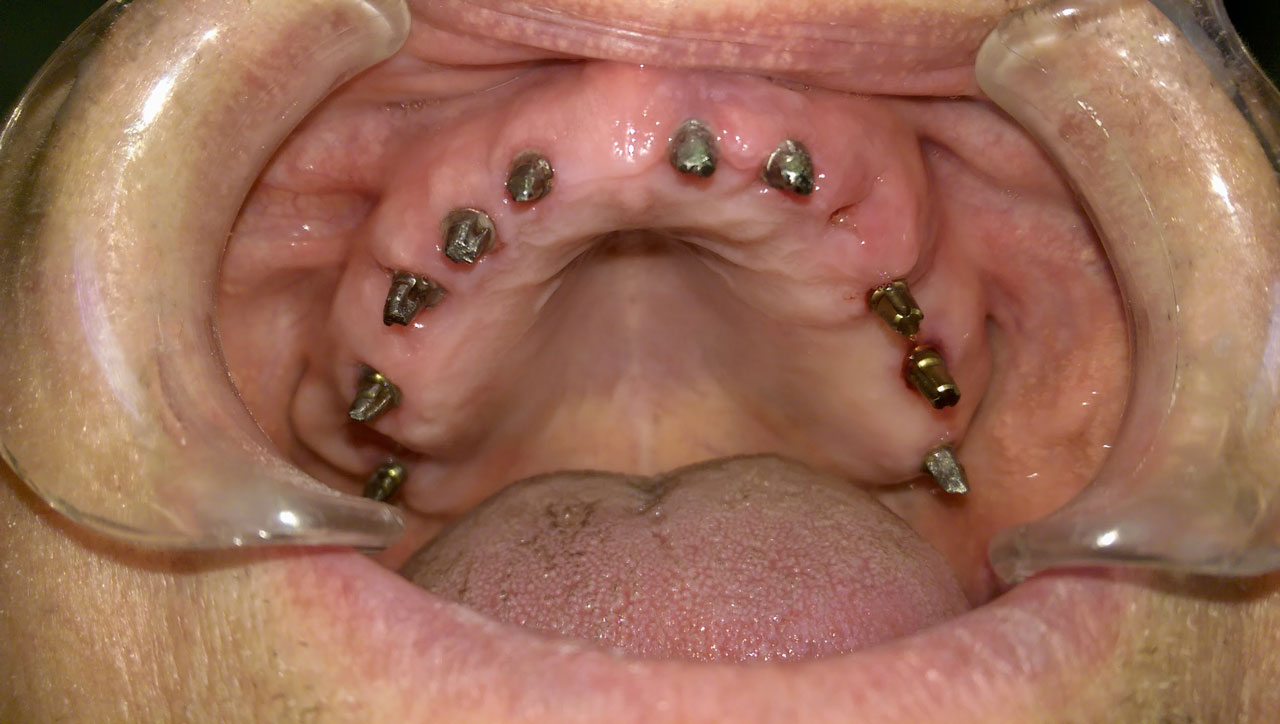

Teljes fogatlanság helyreállítása 2 nap alatt

Teljes fogatlanság helyreállítása 2 nap alatt azonnal terhelhető svájci IHDE implantátumokkal és PMMA műanyag hidakkal. Intraorális szkennerrel vettünk lenyomatot az implantáció után, és erre a digitális mintára készítette el a fogtechnika a hidak digitális tervezését, majd faragta ki műanyagból. Ezt a gyors munkát az azonnal terhelhető implantátumok és a digitális lenyomat, tervezés segítségével tudtuk megcsinálni mindössze 2 nap alatt. Dr. Kelemen Péter és a Symbion Fogtechnika munkája.